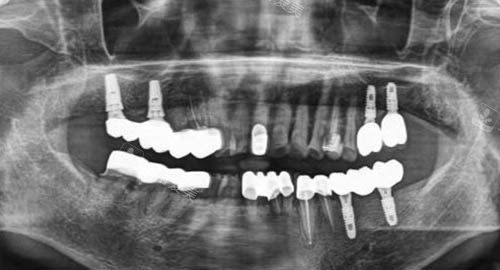

多颗牙齿种植ct

三、种植牙技术是否值得信赖?

恒诚口腔的种植牙技术以“更准一些、稳固、美观”为核心优势。

医院采用国内外比较有名种植体品牌,结合智能化导板技术,确保植入位置更准一些,提高长期可行性。

术中通过不痛管理减轻患者紧张感,术后提供细致护理指导,帮助修复更顺畅。

许多患者反馈,种植后咀嚼功能修复良好,外观自然,使用寿命长,整体体验远超预期。